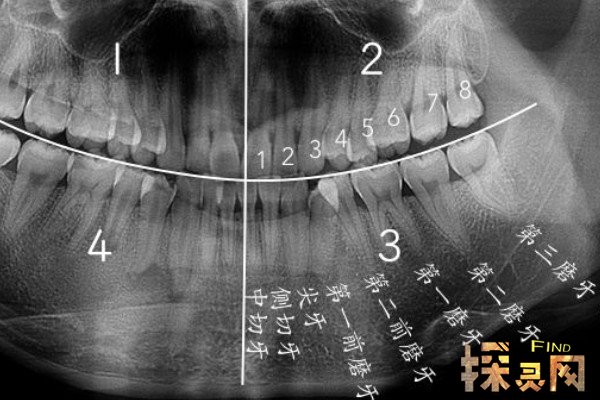

智齿是人类口腔中牙槽骨上最里面的第三磨牙。因为经常会造成疼痛,所以很多人选择拔掉,但是也有人说后悔拔了智齿。那为什么呢?和边肖一起去看看吧。

人们成年后通常会长智齿。生长期可能出现牙龈肿痛,严重影响人们的日常生活。所以很多医生都建议拔智齿,但是拔了之后有些人会后悔不良反应。其实智齿对人的伤害并没有那么大。如果长得好,没必要强行拔除,除非是畸形的智齿。

拔智齿会有一些后遗症。拔掉这颗牙,牙齿之间的缝隙会变大,导致食物残留在缝隙中,形成牙结石后直接造成牙龈问题。另外,智齿拔出后,这个位置的牙槽骨也会被吸收,使门牙松动,进而引发牙周炎。如果不及时治疗,会诱发不良并发症。